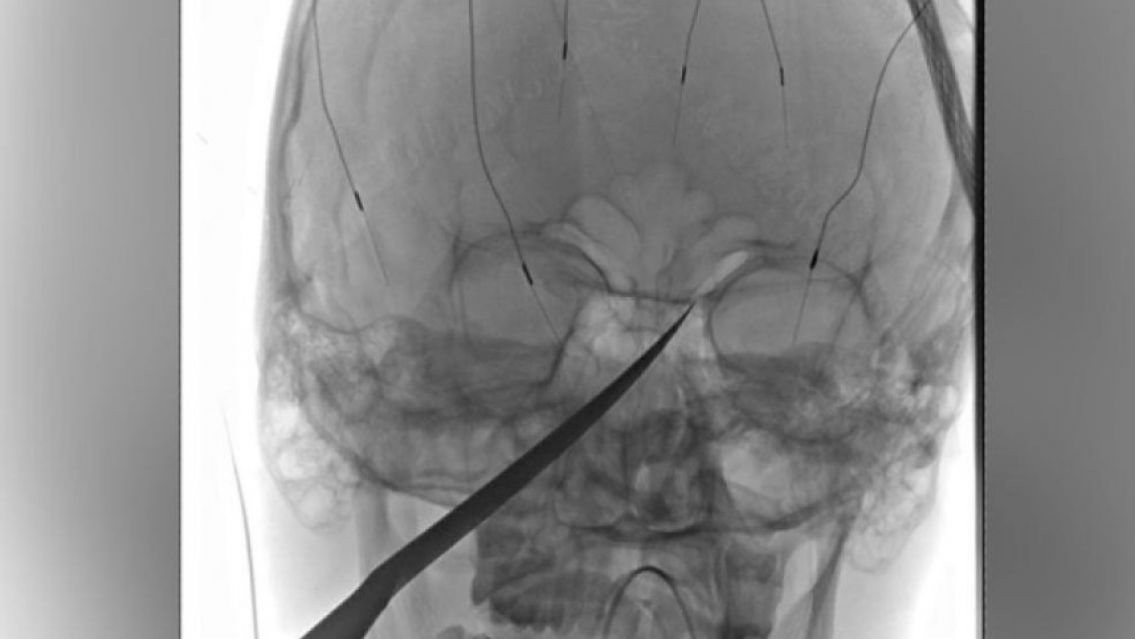

En la madrugada de ayer, en Santa Clara, un hombre de 46 años tuvo que ser hospitalizado después de que su hermano le clavara un cuchillo en la cara durante una discusión.

Según informes, dos hermanos mayores de edad estaban en el interior de la finca cuando comenzó una acalorada discusión. En medio del altercado, uno de los hermanos tomó un cuchillo sierrita y lo clavó en la cara de su hermano, muy cerca del ojo derecho.

El herido logró dirigirse a un destacamento policial cercano para relatar lo sucedido. El Servicio de Atención Médica de Emergencia (SAME) intervino rápidamente y trasladó al herido al Hospital Arturo Zabala de Perico, donde recibió atención médica, fue diagnosticado y sometido a estudios complementarios.